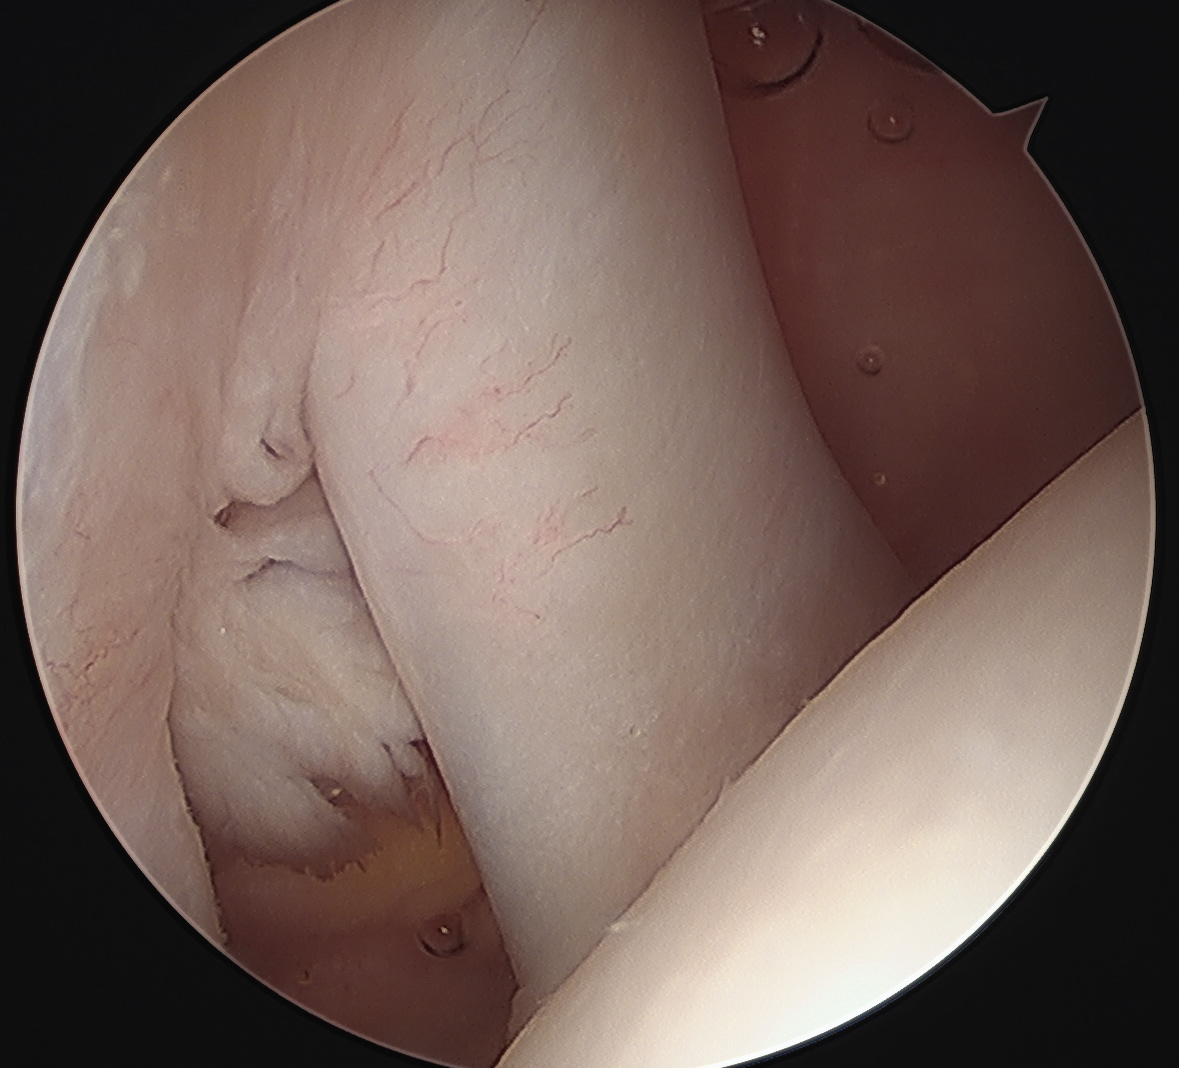

Medially dislocated biceps tendon with upper border subscapularis tear

Full thickness tear of subscapularis off insertion revealed with grasper